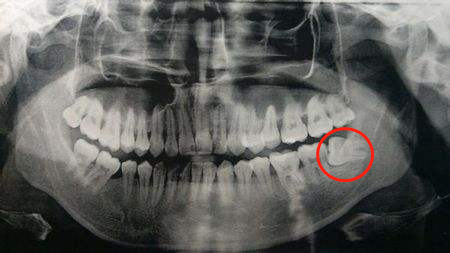

有些拔除智齒較晚的小伙伴(25周歲以上),由于智齒長期椅靠在旁邊的第二磨牙處,使其嚴重受損。

導(dǎo)致第二磨牙的牙槽也嚴重吸收。

這種情況下是可以考慮進行位點保存手術(shù)的。如圖——